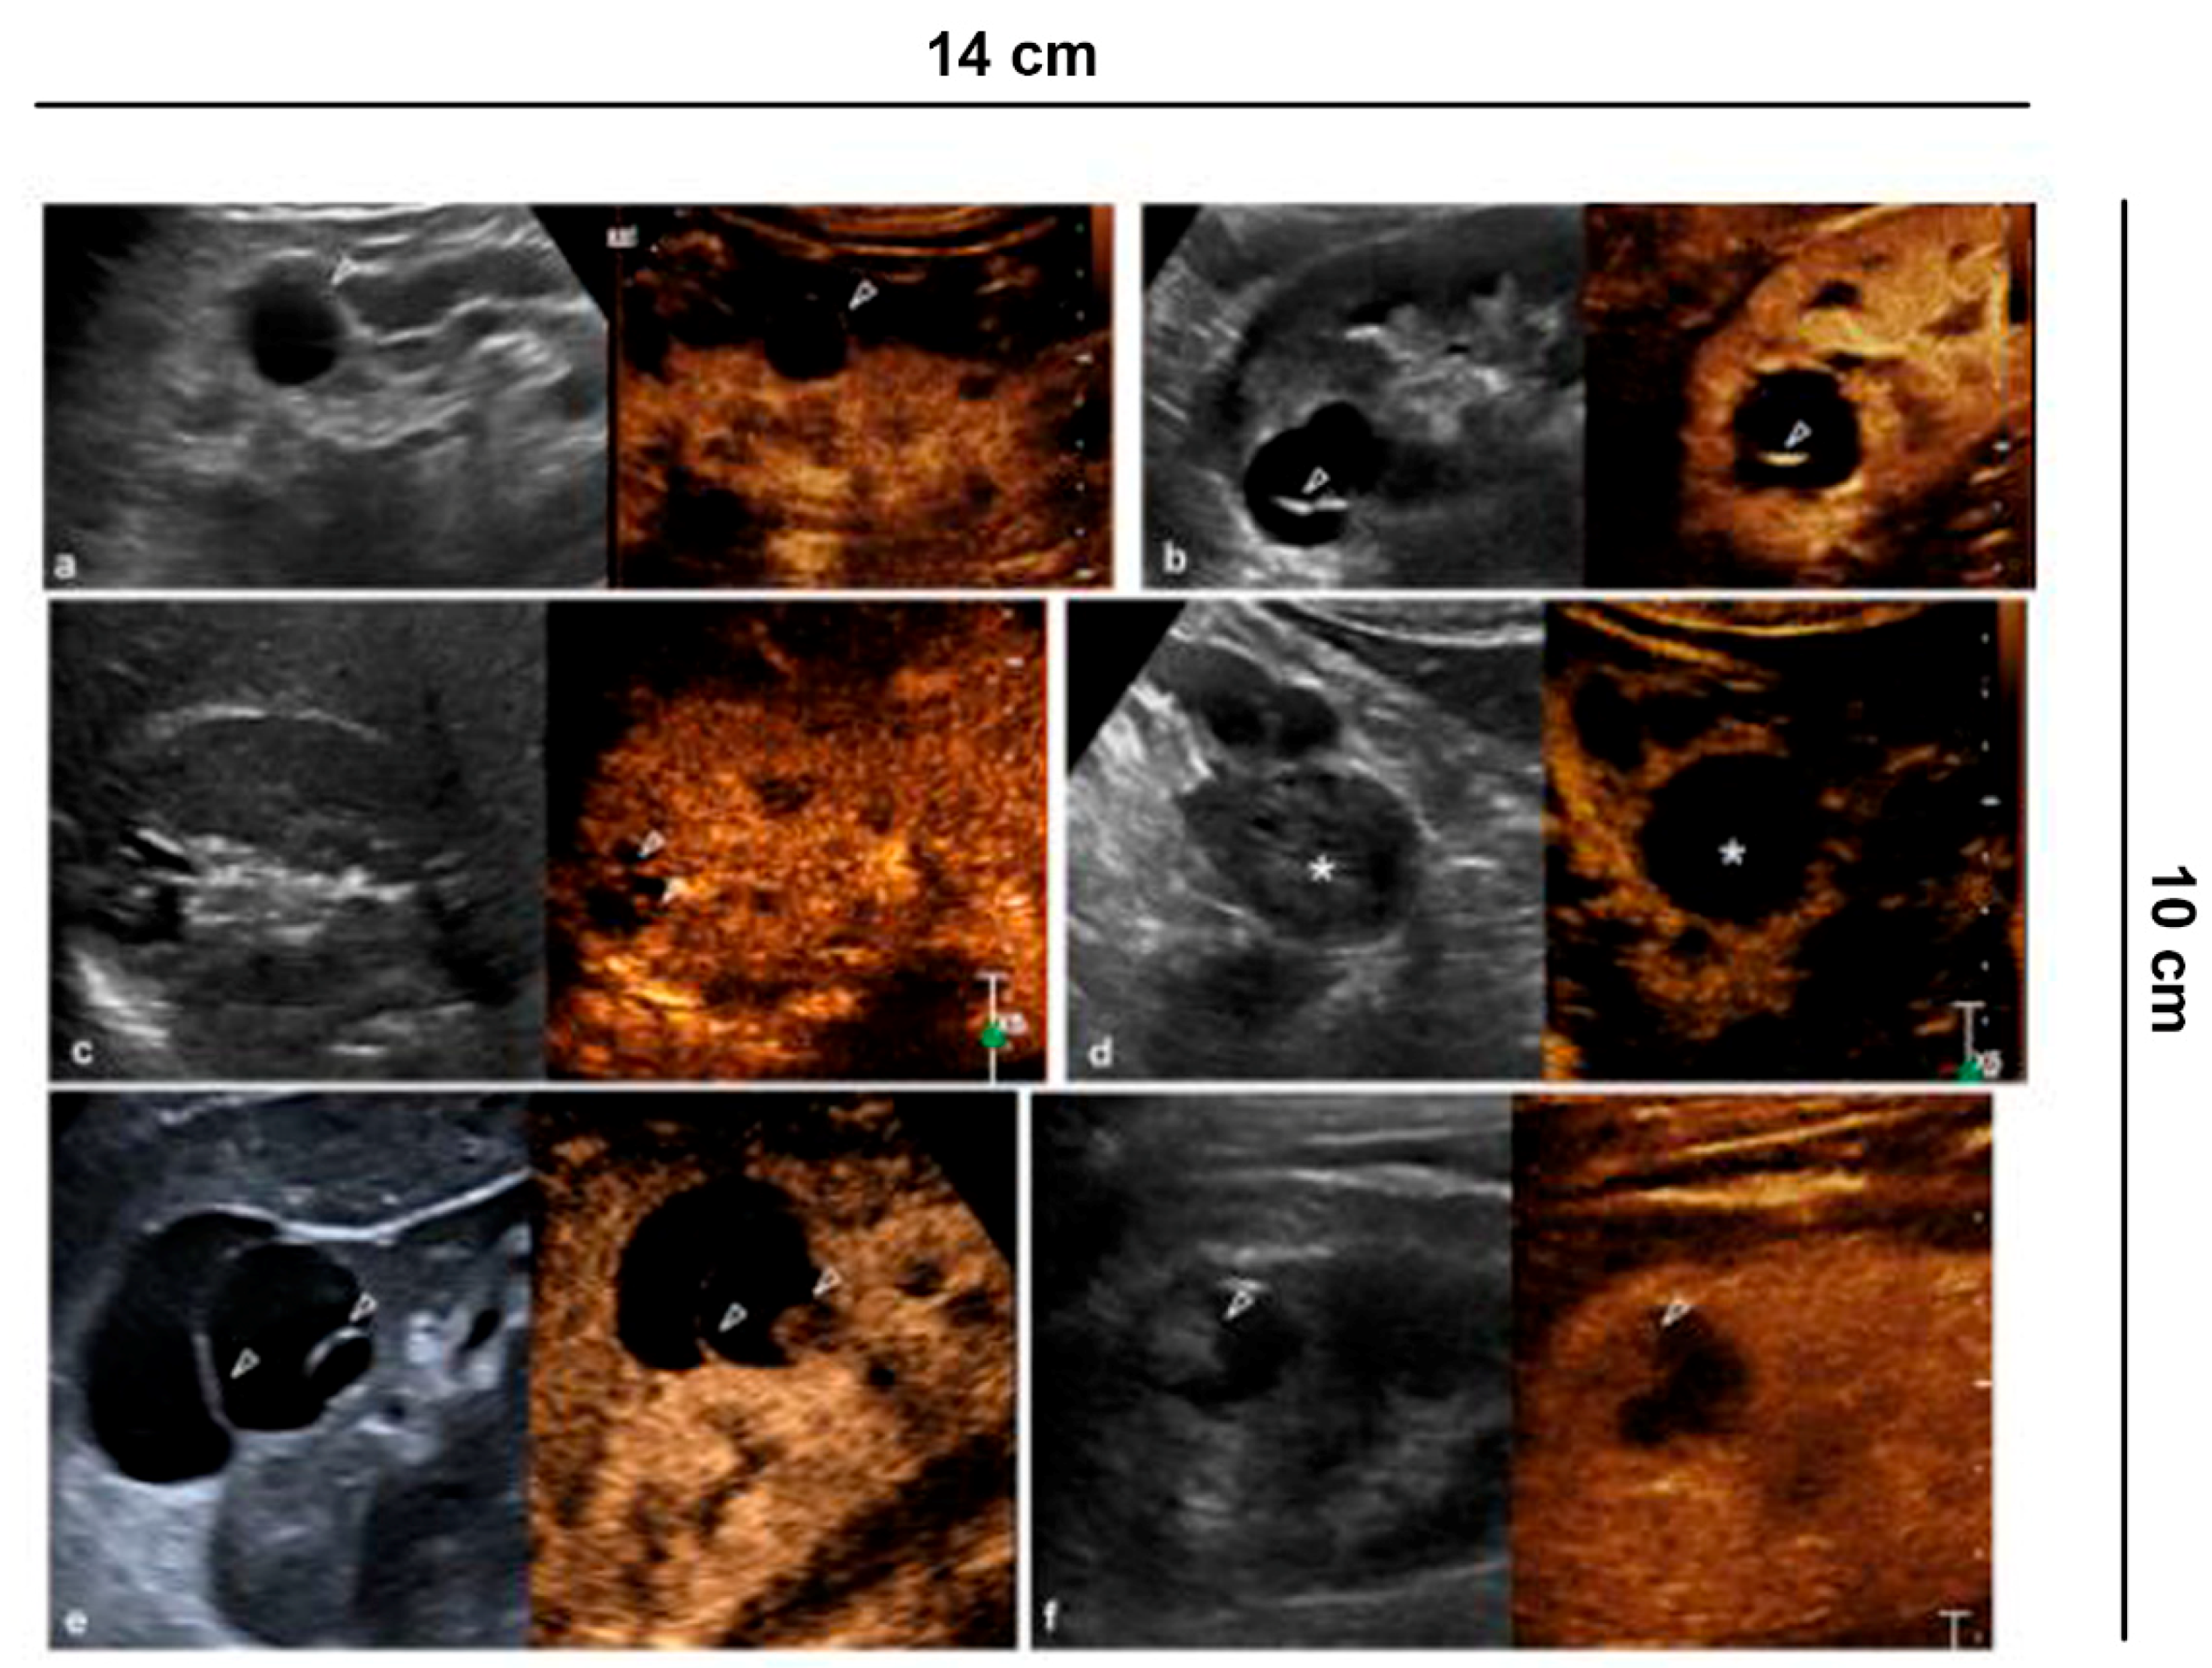

Figure 2.

Characterization of cystic lesions. (a) Bosniak category I cyst (Simple benign cysts): B-mode US and CEUS show anechoic lesion without septa, calcification and wall irregularity; (b) Bosniak category II cyst (Minimally complex benign cysts): minimally complicated cyst with single calcific septum (arrowhead) on B-mode without recognizing enhancement on CEUS; (c) Bosniak category IIF cyst (Presumably benign, imaging surveillance is advised): on US B-mode, cyst with multiple thin septa, minimally thickened (2–3 mm), which on CEUS present minimal enhancement (arrowheads), without irregularities of both the wall and the septa; (d) Bosniak category IIF cyst (Presumably benign, imaging surveillance is advised): echogenic lesion with heterogeneous content inside (asterisk) on B-mode US, which does not show wall enhancement or septa on CEUS; (e) Bosniak category III cyst (Indeterminate lesions): on B-mode, cyst with two septa about 3 mm thick which have thickened, and irregular septa (arrowhead) on CEUS; (f) Bosniak category IV cyst (Likely malignant cystic tumors): cystic lesion with a wall nodule greater than 4 mm (arrowhead).